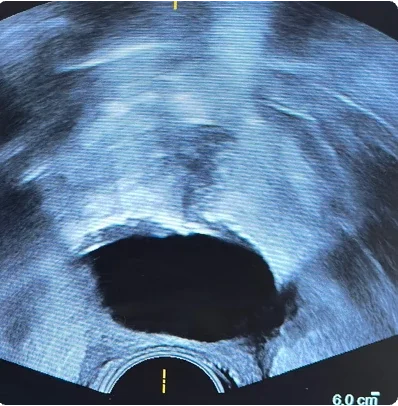

169 cc prostate ultrasound saggital view showing BioProtect Balloon Spacer, prostate, and rectum.

Saggital Ultrasound

Image courtesy of of Dr. Vishesh Agarwal, Radiation Oncologist.